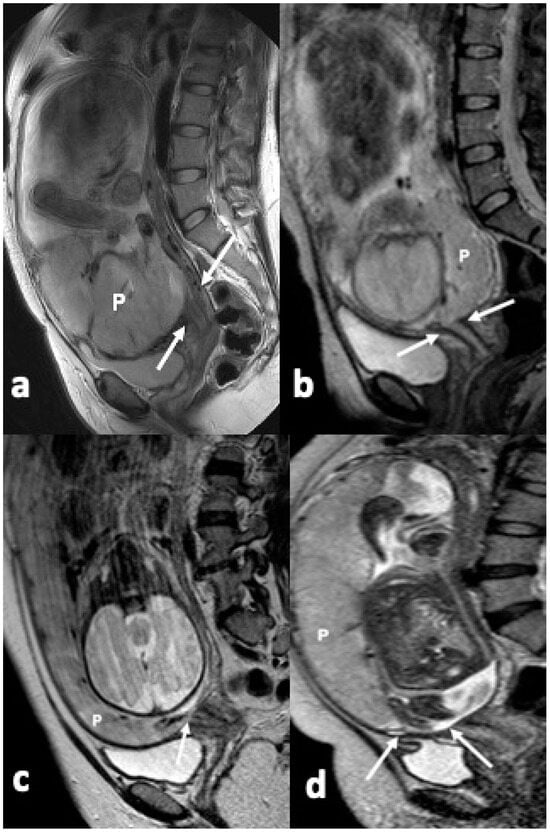

2.2. MRI Protocol

2.3. Image Interpretation